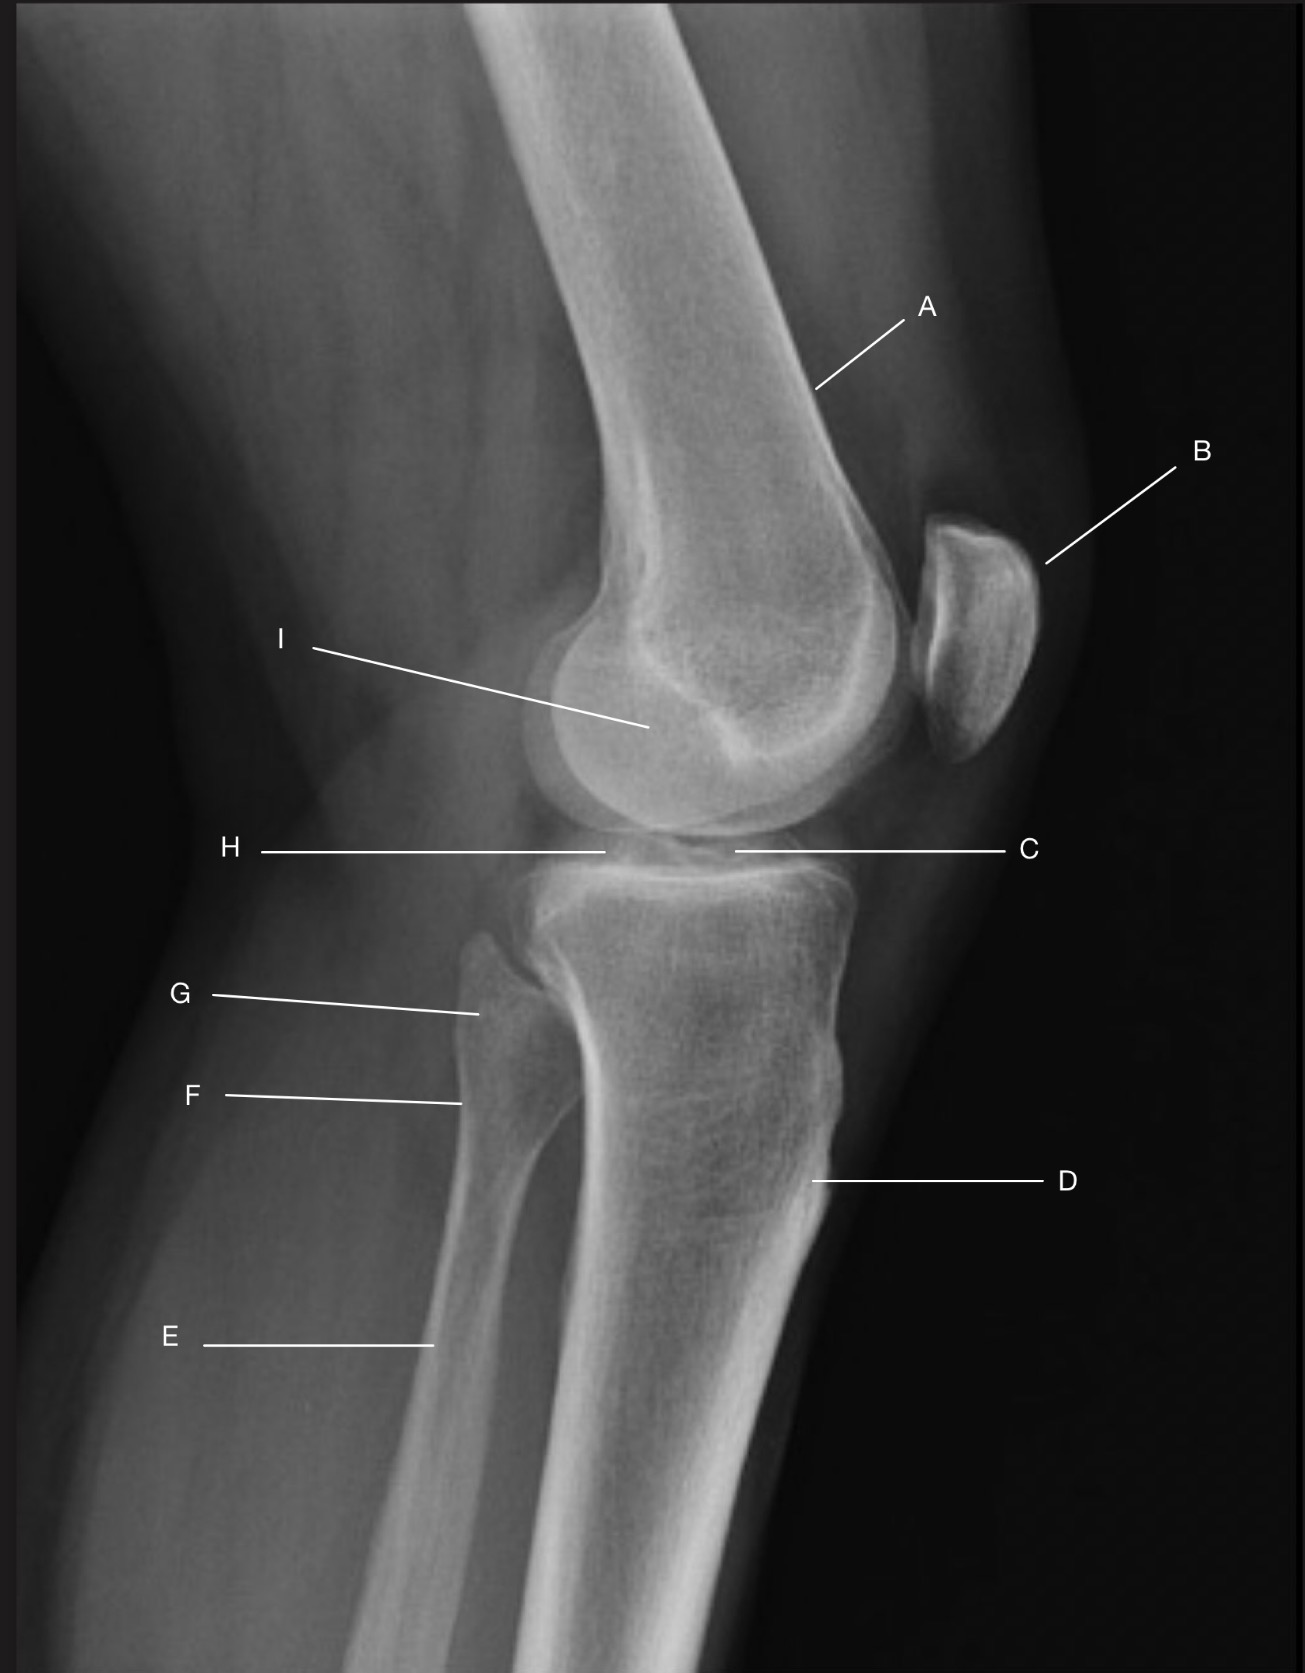

Name the projection.

Should it be repeated, if so why?

Settegast Method or Sunrise View

No.

Label the image.

External cortical surface of patella (not needed for practical)

Patella

Medial facet of patella

Lateral facet of patella

Median patellar ridge

Femoropatellar joint

Medial trochlear ridge

Trochlear groove

Lateral trochlear ridge